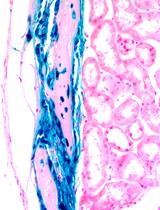

小鼠妊娠期 β 细胞质量的评估

The Assessment of Beta Cell Mass during Gestational Life in the Mouse

YK Yury Kryvalap

JC Jan Czyzyk

1430 Views

Mar 20, 2023

Successful advancement in the treatment of diabetes mellitus is not possible without well-established methodology for beta cell mass calculation. Here, we offer the protocol to assess beta cell mass during embryonic development in the mouse. The described protocol has detailed steps on how to process extremely small embryonic pancreatic tissue, cut it on the cryostat, and stain tissue slides for microscopic analysis. The method does not require usage of confocal microscopy and takes advantage of enhanced automated image analysis with proprietary as well as open-source software packages.